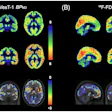

They found that F-18 FDG-PET/CT can be useful in breast cancer management, including initial staging, assessing neoadjuvant systemic treatment response, assessing treatment response in the metastatic setting, searching for loco-regional or metastatic recurrence, and re-staging after therapy, as well as radiation therapy planning.

- Quantitative PET features (SUV, MTV, TLG) are valuable prognostic parameters.

- In baseline staging, F-18 FDG-PET/CT plays a role from stage IIB through stage IV.

- When assessing response to therapy, F-18 FDG-PET/CT should be performed on certified scanners and reported either according to PERCIST, EORTC PET, or EANM immunotherapy response criteria.

- F-18 FDG-PET/CT may be useful to assess early metabolic response, particularly in nonmetastatic triple-negative and HER2+ tumors.

- F-18 FDG-PET/CT is useful to detect the site and extent of recurrence when conventional imaging methods are equivocal and when there is clinical and/or laboratorial suspicion of relapse.